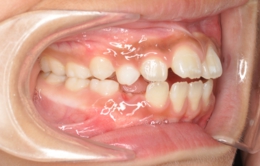

②歯と顎の大きさのバランス

・歯が顎に比べて大きい(逆に言うと顎が小さい)場合歯は凸凹に生えて叢生という状態になります。歯が生えてくる時、早く生えてきたものが場所を占領しますので、多くの場合最後に生えてくる上の犬歯は生える場所が無くなりいわゆる「八重歯」になってしまいます。

・逆に歯が顎に比べて小さい場合、もしくは歯が欠損していたり生えてこないままであったりすると、すきっ歯、空隙歯列弓歯という状態になります。